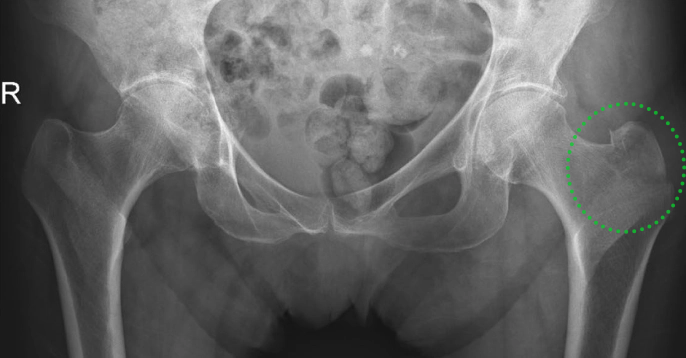

▲ 图示87岁女性患者,摔伤致右髋部疼痛。A:X线检查提示右髋孤立性大转子骨折;B:骨扫描提示孤立性大转子骨折;C:MR提示右股骨粗隆间骨折。